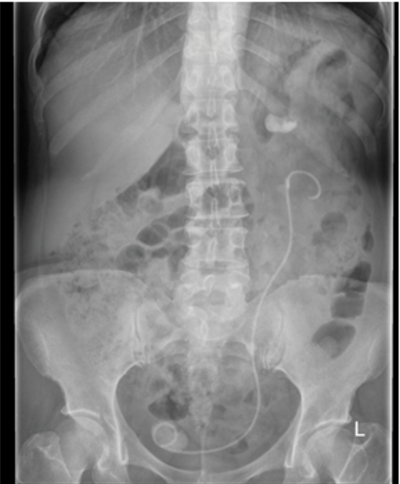

- What x-ray film is this and why is it different from an abdominal x-ray?

- What does the x-ray show?

- What percentage of urinary tract stones are radio-opaque and what are their likely compositions?

- What x-ray images are normally required for an IVU?

- What contrast media is required for an intravenous urogram (IVU) and what is the radiation dose of an IVU?

-

KUB x-ray (kidney / ureter / bladder). Film is taken at oblique angle so the patient’s pelvis is easily demonstrated / imaged, whereas an AXR is taken horizontally.

Left ureteric stent in-situ with calcified lower end, left mid ureteric stone and a large left upper pole stone.

75-85% are radio-opaque, calcium containing stones eg Calcium oxalate or calcium phosphate.

Plain KUB, immediate nephrogram, five minute film, 10 minutes, 20 minutes and a post-micturition study +/- delayed films if required. 5. Non-ionic, low-osmolality contrast agent (e.g. Omnipaque 1ml/Kg), 2.5mSv.